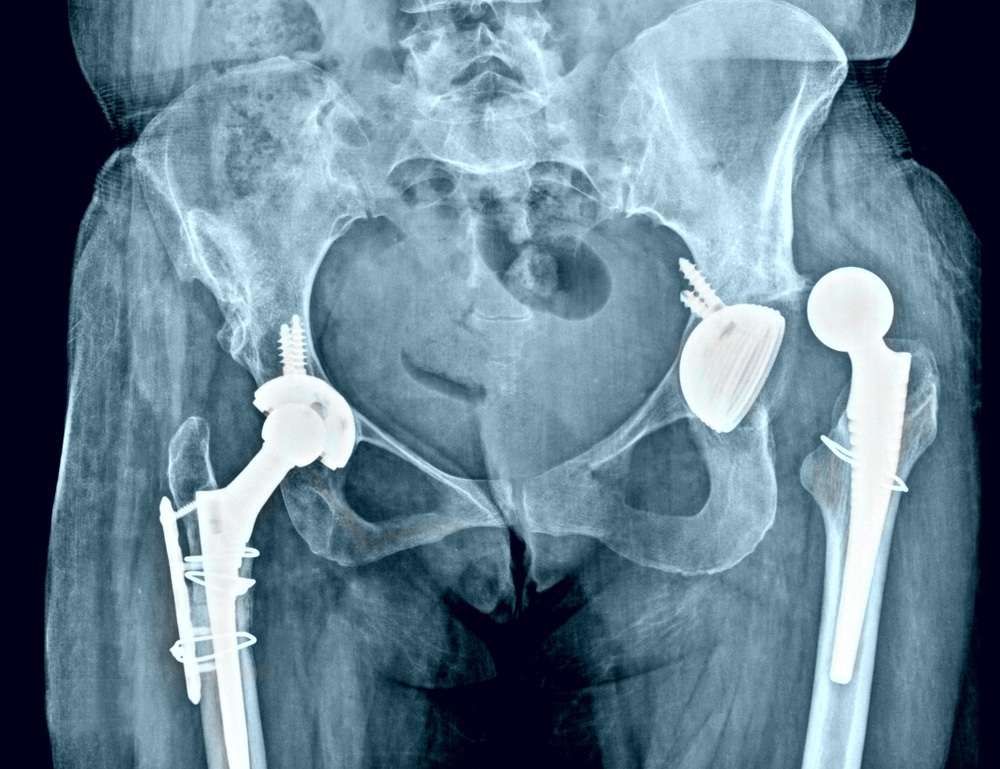

Η αναθεώρηση αρθροπλαστικής ισχίου είναι η χειρουργική διαδικασία αντικατάστασης μιας υπάρχουσας πρόθεσης ισχίου με νέα. Αυτό μπορεί να περιλαμβάνει την αντικατάσταση ολόκληρης της πρόθεσης ή μόνο συγκεκριμένων τμημάτων της, όπως το κοτυλιαίο εμφύτευμα ή το μηριαίο στέλεχος.

Η αρθροπλαστική ισχίου αποτελεί μια σύγχρονη χειρουργική επέμβαση, η οποία απαλλάσσει τους ασθενείς από τα συμπτώματα που προκαλεί η παθολογία του ισχίου και ιδιαίτερα η οστεοαρθρίτιδα. Η φθαρμένη άρθρωση του ισχίου αντικαθίσταται από τεχνητά εμφυτεύματα(προθέσεις). Με τον τρόπο αυτό αποκαθίσταται η κινητικότητα του ισχίου και ο ασθενής απαλλάσσεται από τα συμπτώματα που υποβαθμίζουν την ποιότητα ζωής του.

- Ακτινογραφίες ισχίου: Απαραίτητες για την αξιολόγηση της θέσης και της κατάστασης της πρόθεσης, καθώς και για την ανίχνευση πιθανών καταγμάτων ή οστικής φθοράς.

- Εμφύτευση της νέας πρόθεσης: Τοποθέτηση της νέας πρόθεσης, η οποία μπορεί να απαιτεί εξειδικευμένα εμφυτεύματα, ειδικά σε περιπτώσεις σημαντικής οστικής απώλειας.